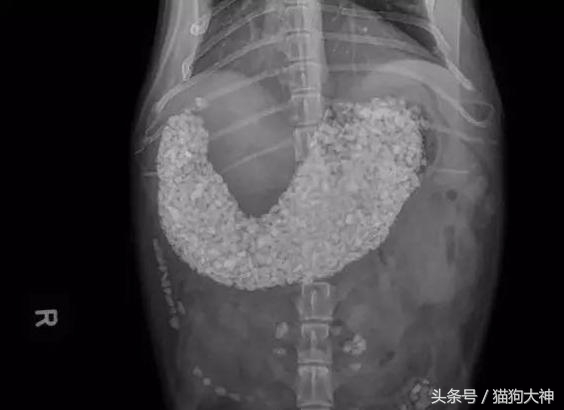

比如这只狗狗,就把自己当成了存钱罐,吞了这么多硬币。

这是一只12岁柯基的胃,由于患上的异食癖,吃了一堆家里盆栽里的土和小石子,把胃都塞满了。这不是一天两天造成的,吃下一堆不能消化的东西狗狗一般会食欲不振,没有精神或排泄困难等表现,如果主人早点关注到,就不会这么严重了。